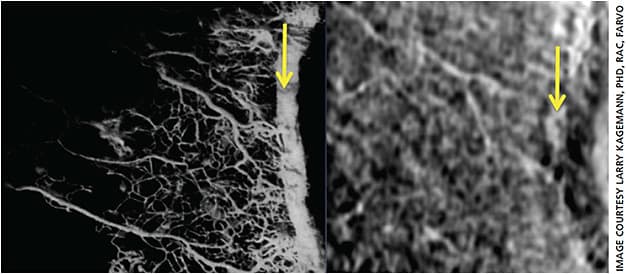

More recent resin castings of the outflow pathway in owl and cynomolgus monkey eyes reveals Schlemm’s canal at physiological pressures (Figure 3).11 It is possible that this is a more physiological representation of Schlemm’s canal. We will see that this presentation is consistent with that obtained in “virtual castings” of the same structures in living human eyes.12

The angiography technique has recently been demonstrated in living human eyes. Huang et al. have published the first series of outflow angiograms in human subjects.22 While the images provide excellent visualization of gross structures in the outflow pathway, this invasive technique does not appear to capture greater detail than that provided by the noninvasive technique of “virtual casting” or mapping of scleral voids. (Figure 9) However, the mapping of scleral voids cannot ensure that only outflow vasculature is imaged. Angiography of the outflow pathway provides a high degree of confidence that the resultant imagery contains only those vessels distal to Schlemm’s canal.